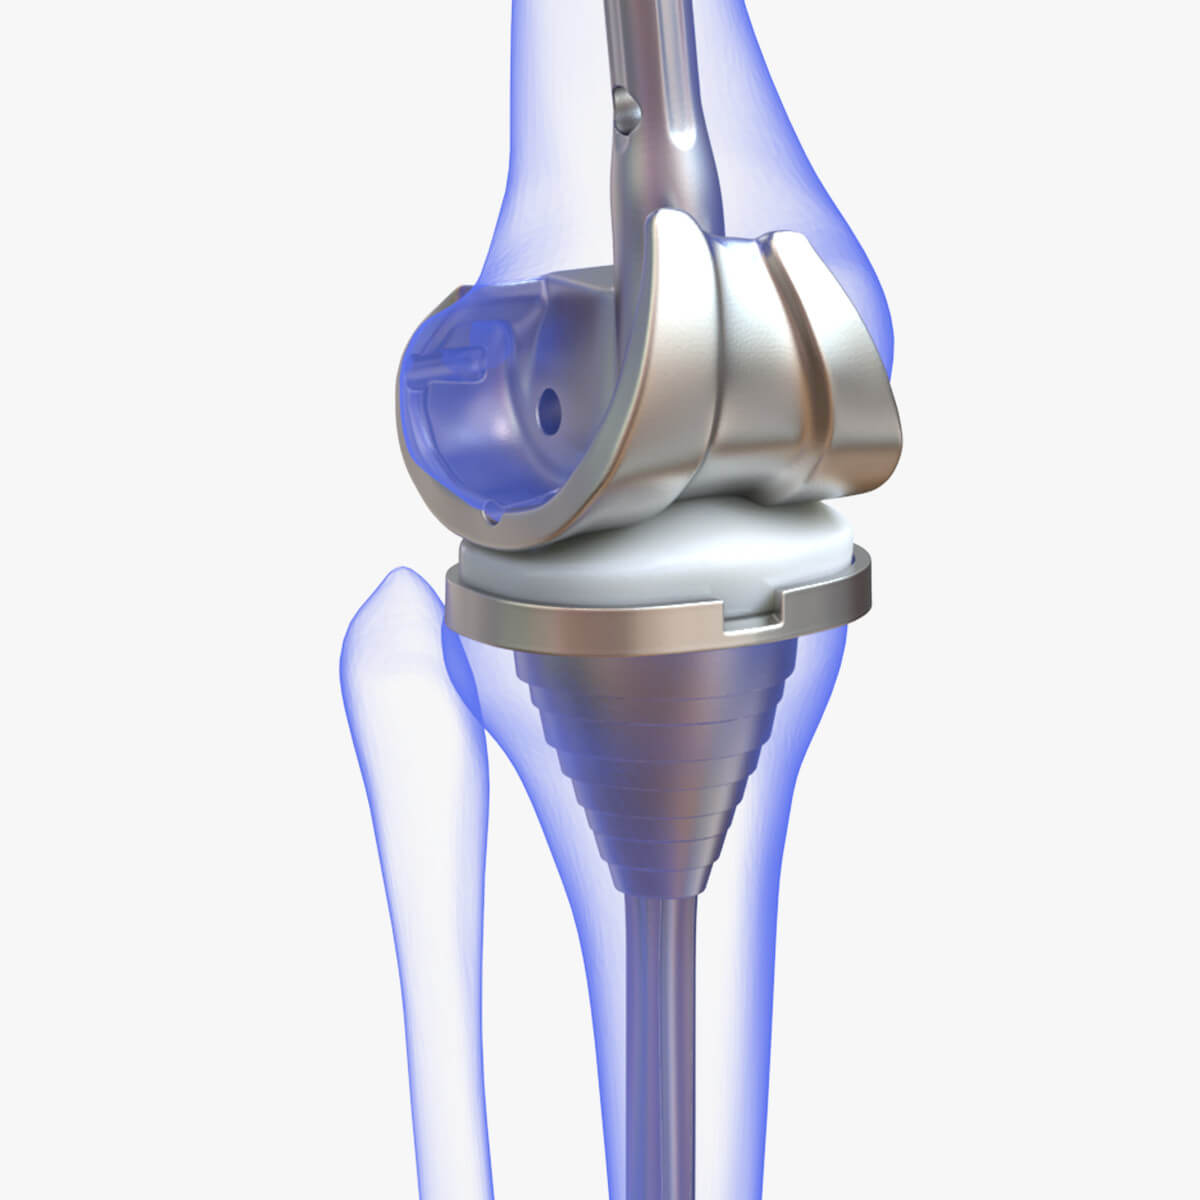

For severe joint damage from conditions like osteoarthritis or injury, Dr. Harish Talreja performs joint replacement surgeries, such as knee or hip replacements.

Knee Replacement

Hip Replacement

Knee Replacement

Hip Replacement